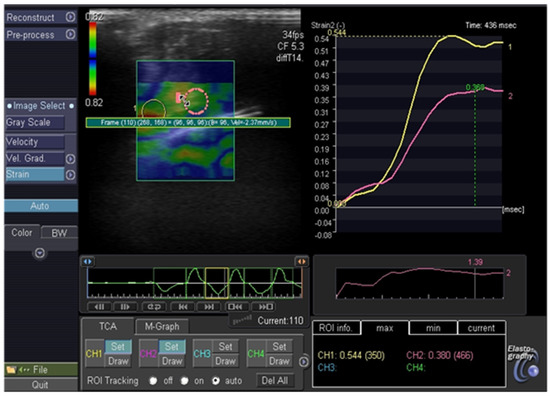

- Dietrich, C.F.; Barr, R.G.; Farrokh, A.; Dighe, M.; Hocke, M.; Jenssen, C.; Dong, Y.; Saftoiu, A.; Havre, R.F. Strain Elastography—How to do it? Ultrasound Int. Open 2017, 3, E137–E149. [Google Scholar] [CrossRef] [PubMed]

- Monpeyssen, H.; Tramalloni, J.; Poirée, S.; Hélénon, O.; Correas, J.M. Elastography of the thyroid. Diagn. Interv. Imaging 2013, 94, 535–544. [Google Scholar] [CrossRef] [PubMed][Green Version]

- Carneiro-Pla, D. Ultrasound Elastography in the evaluation of thyroid nodules for thyroid cancer. Curr. Opin. Oncol. 2013, 25, 1–5. [Google Scholar] [CrossRef] [PubMed]

- Borysewicz-Sanczyk, H.; Dzieciol, J.; Sawicka, B.; Bossowski, A. Practical Application of Elastography in the Diagnosis of Thyroid Nodules in Children and Adolescents. Horm. Res. Paediatr. 2016, 86, 39–44. [Google Scholar] [CrossRef]

- Cunha, G.B.; Marino, L.C.I.; Yamaya, A.; Kochi, C.; Monte, O.; Longui, C.A.; Cury, A.N.; Fleury, E.D. Elastography for the evaluation of thyroid nodules in pediatric patients. Radiol. Bras. 2019, 52, 141–147. [Google Scholar] [CrossRef]